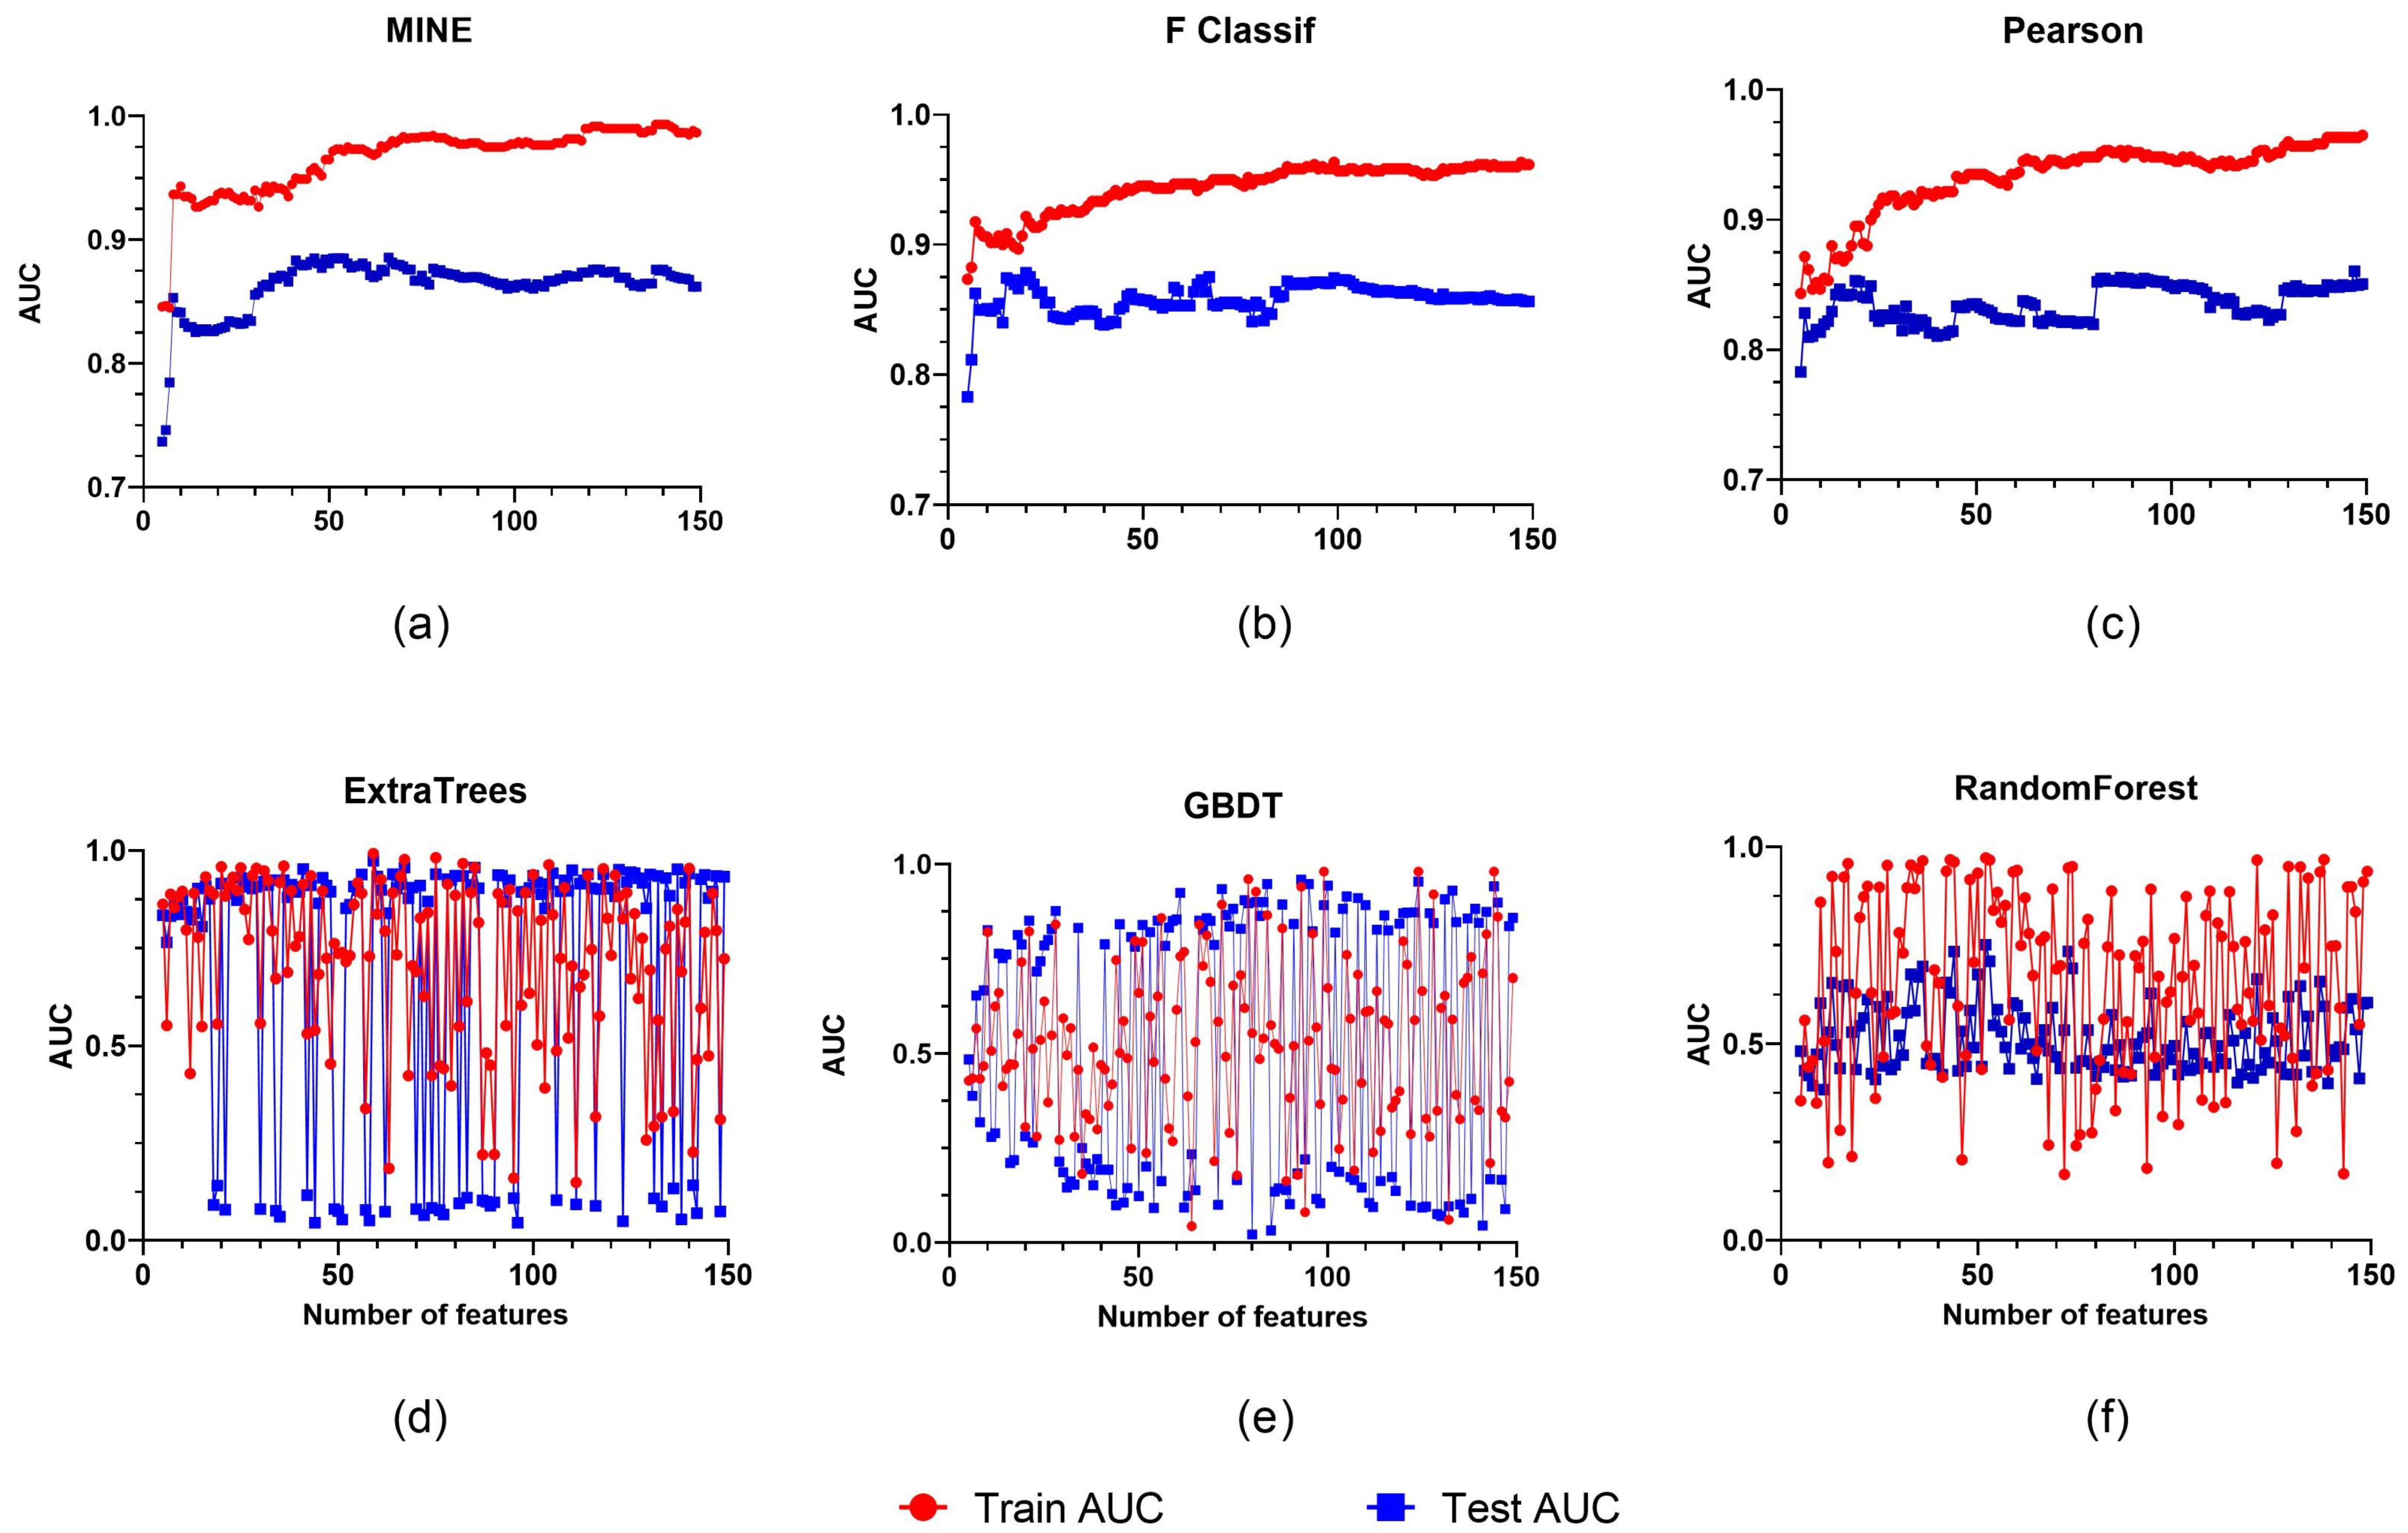

2.4. Radiomics Feature Selection and Development of the Radiomics Model

3.2. Feature Selection and Performance of the Clinical Model and Radiomics Model